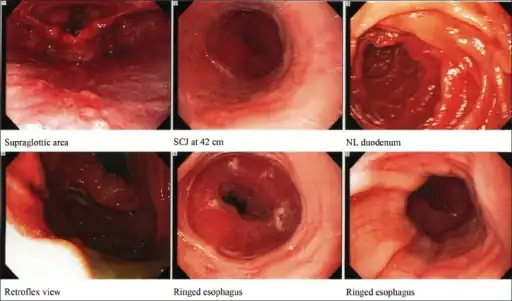

Concentric rings in the distal esophagus, consistent with eosinophilic esophagitis

Endoscopic image of esophagus in a case of eosinophilic esophagitis. Concentric rings are termed trachealization of the esophagus.

Endoscopy

Endoscopically, ridges, furrows, or rings may be seen in the esophageal wall. Sometimes, multiple rings may occur in the esophagus, leading to the term "corrugated esophagus" or "feline esophagus" due to similarity of the rings to the cat esophagus. Presence of white exudates in esophagus is also suggestive of the diagnosis.[18] On biopsy taken at the time of endoscopy, numerous eosinophils can be seen in the superficial epithelium. A minimum of 15 eosinophils per high-power field are required to make the diagnosis. Eosinophilic inflammation is not limited to the esophagus alone, and does extend through the whole gastrointestinal tract. Profoundly degranulated eosinophils may also be present, as may micro-abscesses and an expansion of the basal layer.[3][15]